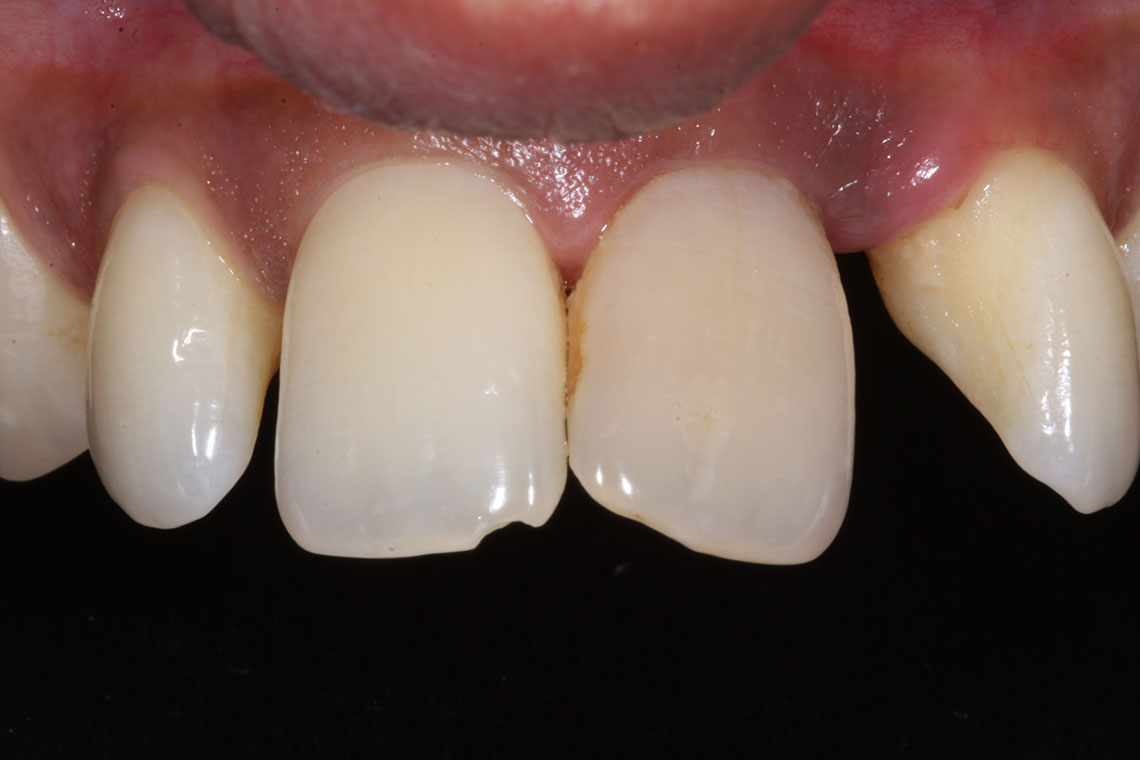

This lovely lady attended with very low confidence due to her teeth and smile. Gum disease and trauma had led to the teeth drifting. One of her front teeth was so loose that it needed to be replaced. We started by providing intensive treatment with our dental hygienist to treat the gum disease. Following this Invisalign® braces were used to align the teeth and the teeth were whitened. A dental implant was then placed to replace the loose front tooth and composite bonding was performed to the adjacent front tooth. The change in the patient’s confidence as a result of this work was breathtaking.